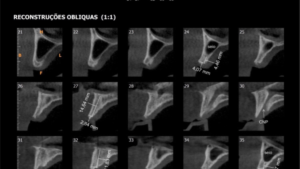

PLANEJAMENTO DIGITAL DOS IMPLANTES

Na odontologia moderna , as tecnologias e exames possibilitam planejamentos mais precisos e conservadores. O planejamento digital possibilita a analise de posicionamento permitindo a colocação de implantes com segurança e precisão.

O Planejamento digital, as cirurgias guiadas , trazem segurança e tornam os procedimentos menos invasivos .